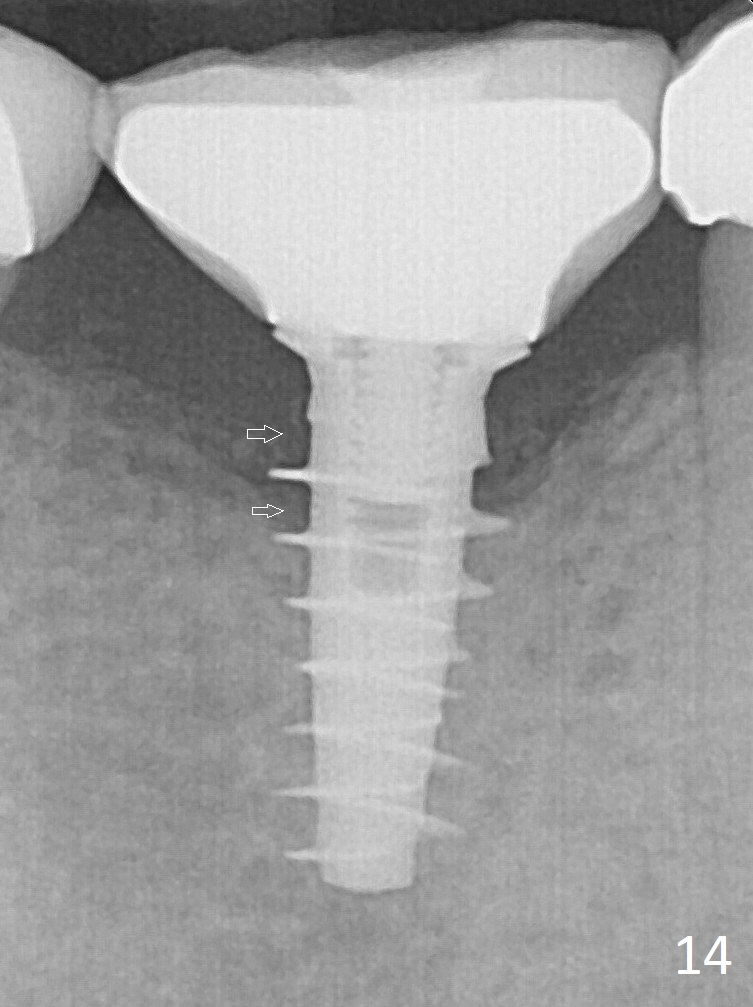

PA is taken immediately post tightening and cementation (Fig.14, 5 months postop).  It appears that new bone has grown between the most coronal threads (arrows).